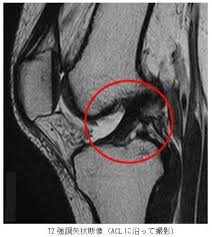

そして、関節の検査では、靭帯や軟骨といった柔らかい組織を調べることができます。レントゲンでは主に骨の評価が中心となりますが、MRIでは関節の中の状態まで確認できるのが大きな強みです。

関節(膝・肩など)